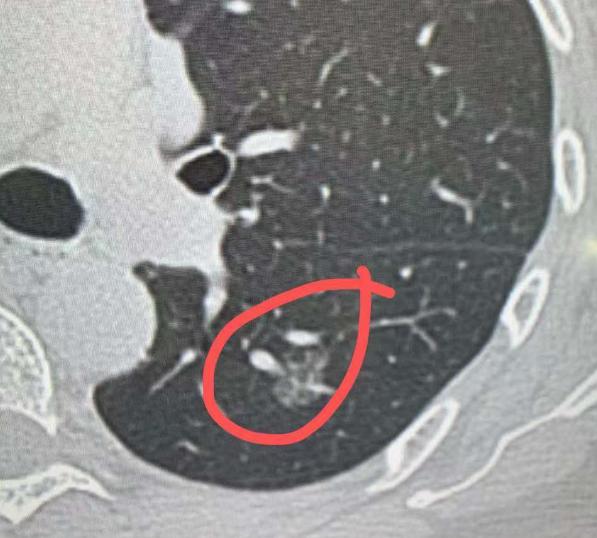

4mm磨玻璃结节,术后确诊肺微浸润癌?不少朋友查出几毫米的肺磨玻璃结节,还听说可能是原位癌、微浸润癌,就急着来找我,反复要求尽快手术切除,生怕耽误病情。 其实大家有这种焦虑情绪完全能理解,但对于小于5mm的肺微小结节,诊疗原则并不是一发现就切。 哪怕从影像学形态上高度怀疑是原位癌或微浸润癌,只要经过定期随访没有明显变化,单纯随访观察就足够安全,没必要盲目手术。 很多人会疑惑,既然都定性为“癌”了,为什么还能放任不管? 核心还是要权衡治疗收益和肺功能损伤。肺是人体重要的呼吸器官,每一部分肺组织都有其功能,为了一个几毫米的微小病灶,就切除周围大片正常肺组织,反而会影响后续呼吸功能,得不偿失。 尤其是这类惰性病灶,生长速度极其缓慢,长期随访无变化的情况下,不会对健康造成威胁,持续观察反而更稳妥。 也有患者跟我说,看我之前也做过4mm、5mm的肺结节手术,为什么自己的小结节就不建议切? 这里要明确,5mm以下结节是否手术,关键看切除操作对肺功能的损伤程度,不能一概而论。 手术决策需要结合结节位置、数量、患者整体情况综合判断,不是只看结节大小。 我之前接诊过一位60多岁的患者,左肺长了多个磨玻璃结节,其中左下肺背段的结节直径达1.5cm,不仅体积大,位置也比较表浅,适合手术切除,于是为她制定了左下肺段切除手术方案。 同时检查发现,她左上肺还有两个纯磨玻璃结节,分别是4mm和5mm,且都靠近肺外周,切除时仅需少量剥离周围肺组织,对肺功能影响极小。 最终手术中,我们在完成左下肺结节切除的同时,一并将这两个小结节切除,一次手术解决了三个病灶。术后冰冻病理结果显示,这两个小结节均为微浸润癌。 之所以一起切除,是因为患者本身就要接受左肺手术,在肺损伤可控的前提下,顺带清除同侧可疑恶性结节,既能避免后续二次手术,也能彻底消除患者顾虑。 总而言之,对于肺多发结节,手术决策的核心是平衡治疗效果与肺功能保护。单侧肺内若存在多个可疑恶性结节,在主病灶需要手术、且小结节切除对肺损伤较小的情况下,会尽量在一次手术中完整切除,最大程度保障患者健康。 但对于孤立的5mm以下微小结节,只要随访稳定,就无需过度焦虑,定期复查即可。[玫瑰][作揖]